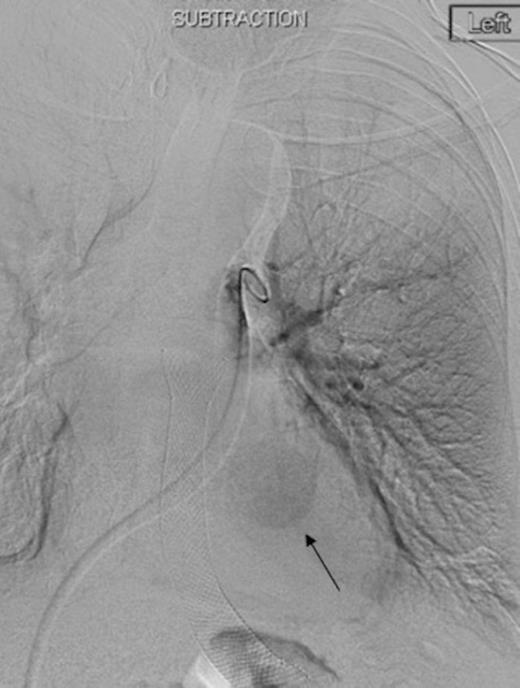

Selective digital subtraction angiography image of left lower lobe pulmonary artery, demonstrating filling of the inflammatory aneurysm and depicting the feeding branches clearly

Digital subtraction angiography post deployment of the AVP 4 device in the PA branch feeding the aneurysm (arrow). No residual or collateral filling seen